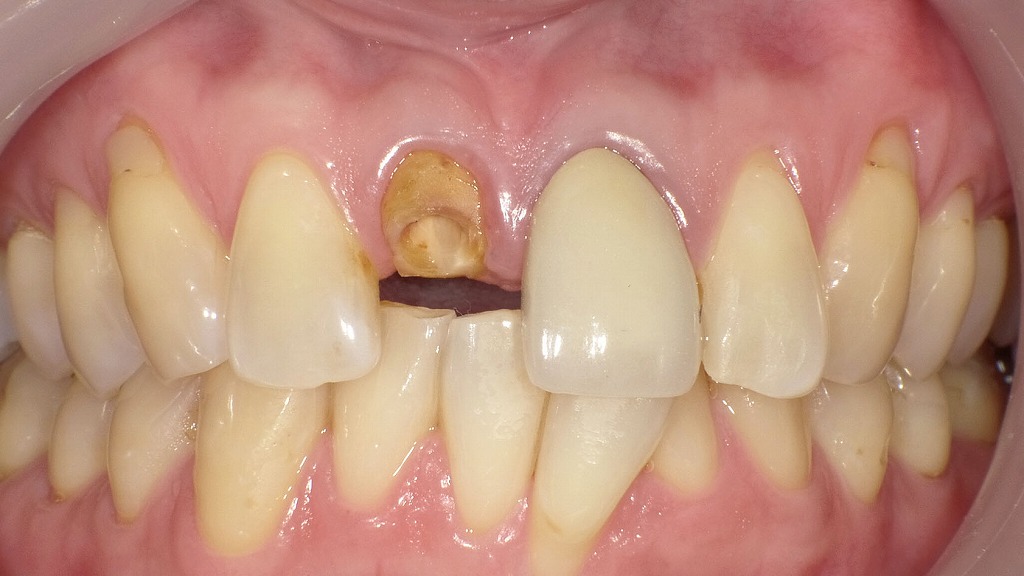

前歯が折れた症例とメタルボンドによる治療後の変化

前歯が折れて歯質を大きく失っていた症例に対し、メタルボンドクラウンを用いて機能と審美性の回復を行いました。内側に金属を使用することで強度を確保し、外側はセラミックで覆うため、前歯でも自然な見た目が得られます。咬合の安定と長期的な耐久性を重視した治療結果です